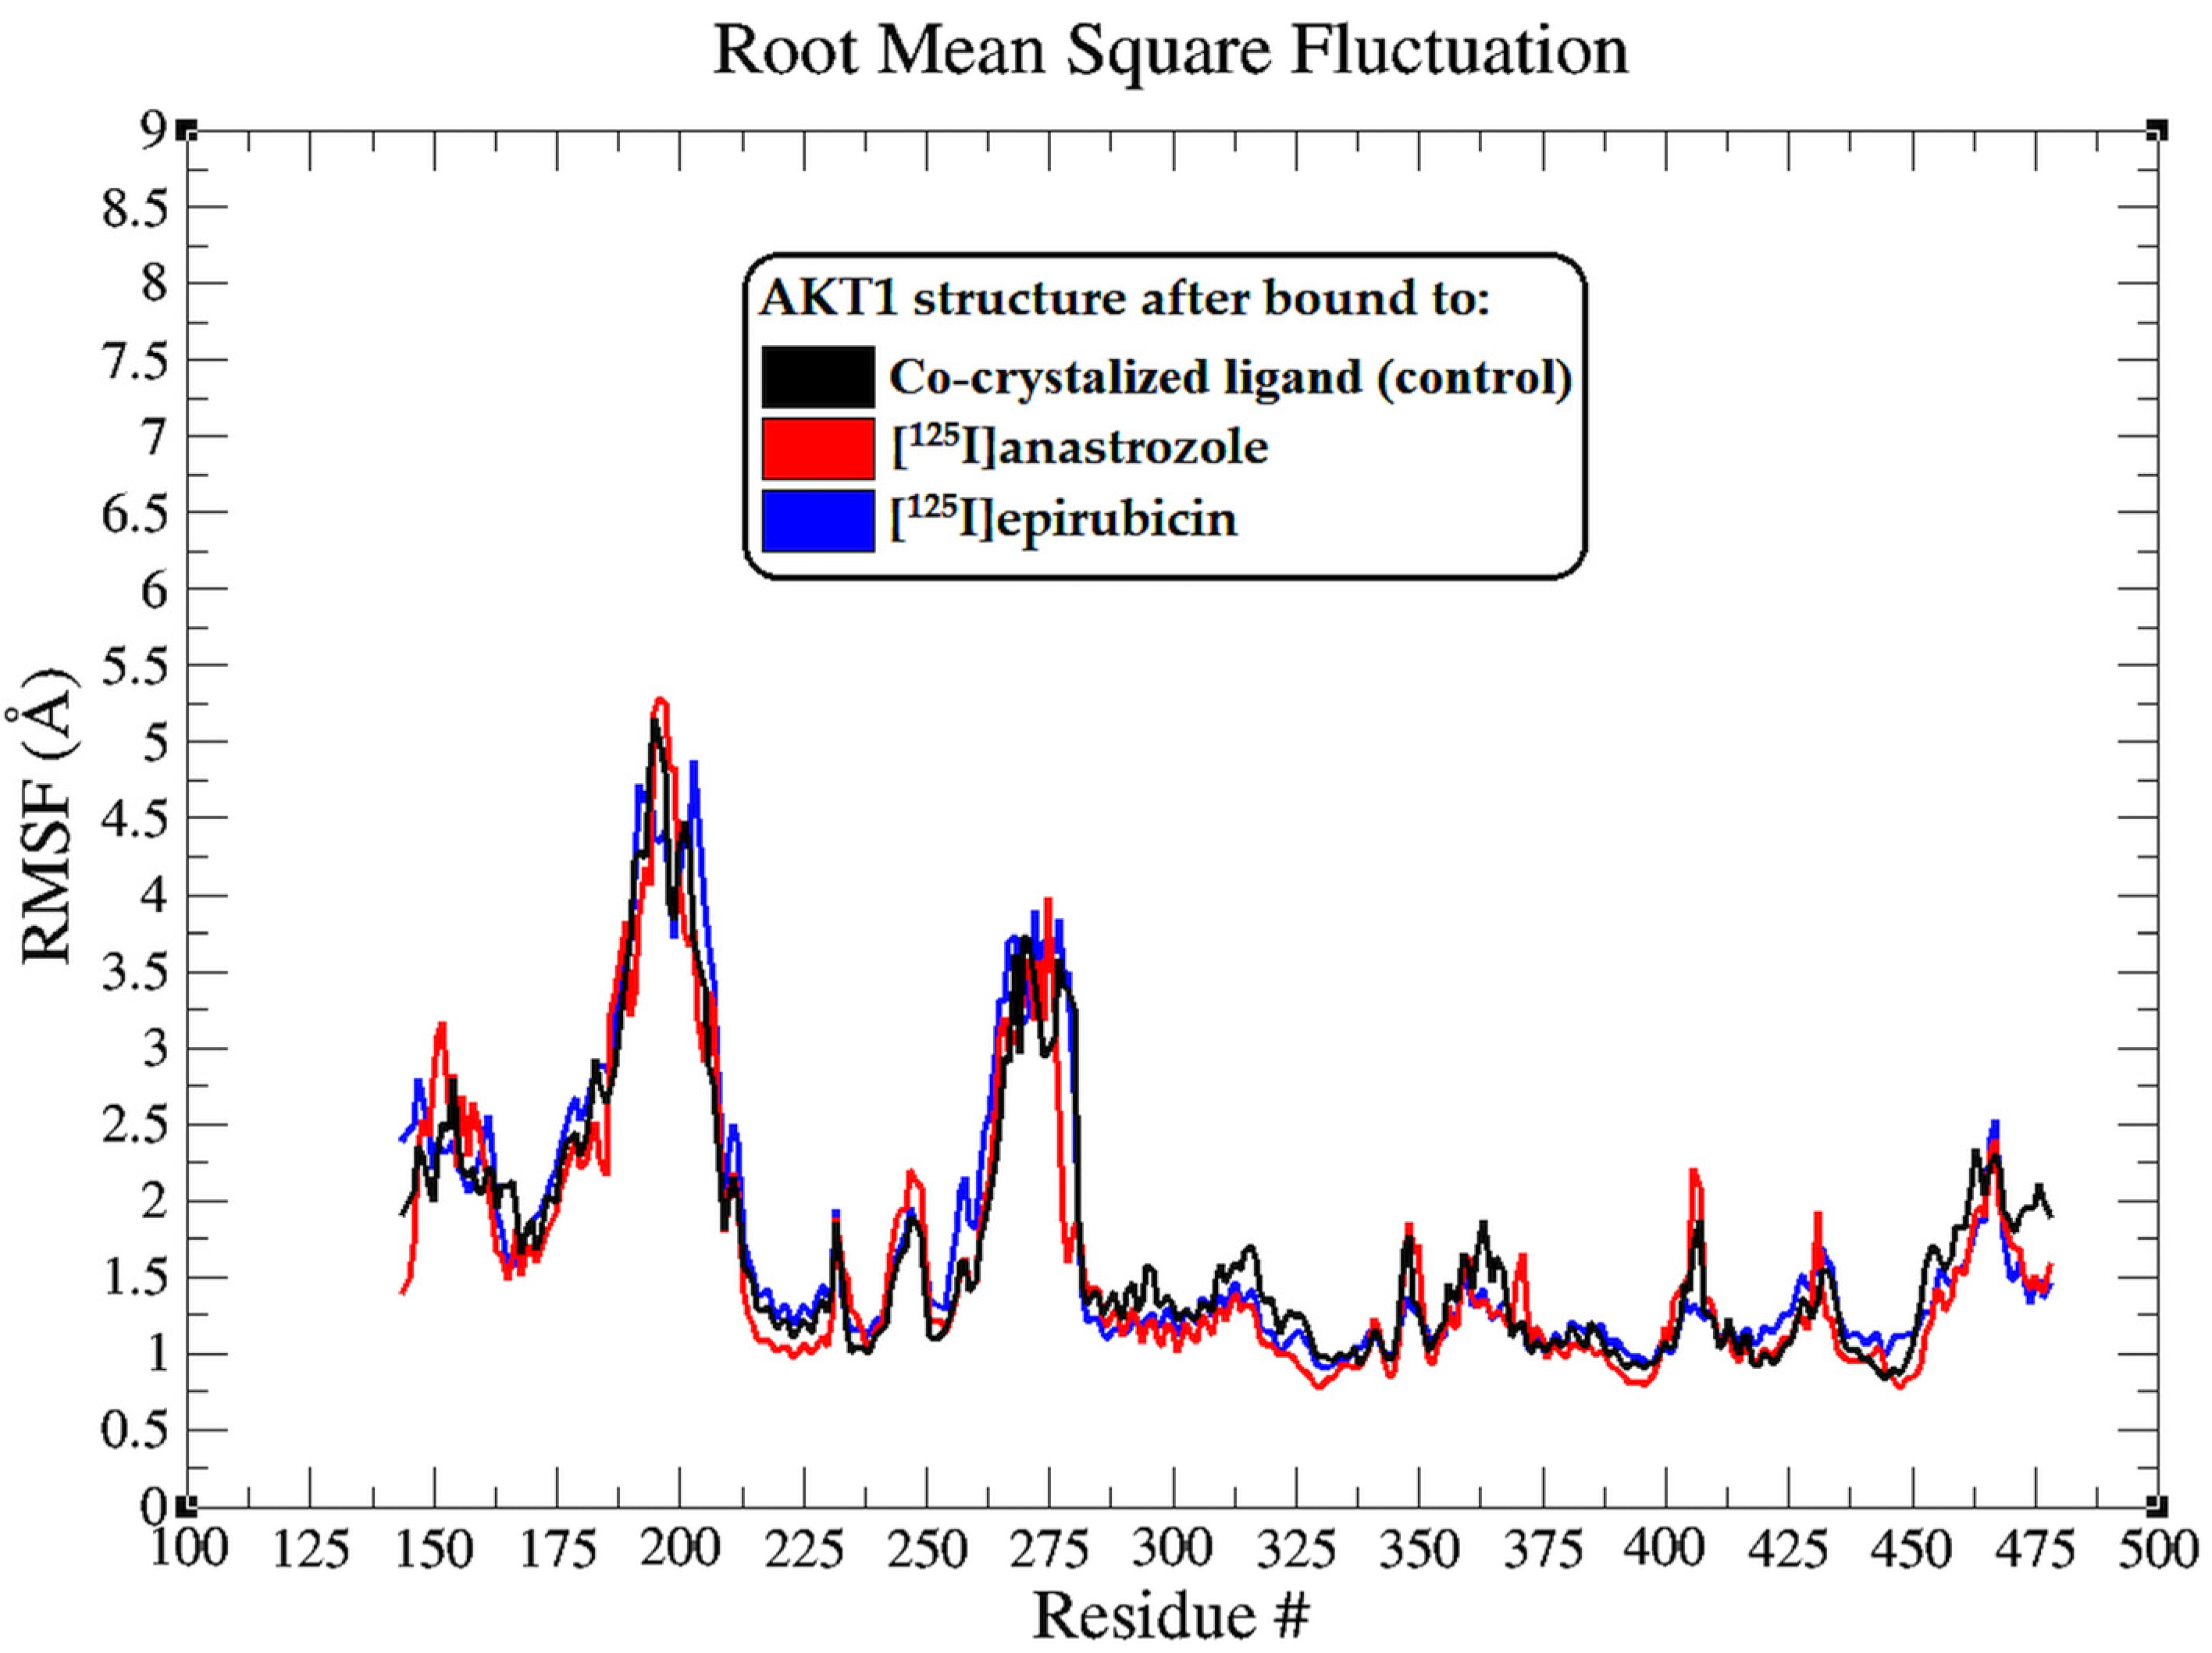

2.2. Molecular Dynamic Simulation

3.2. Molecular Dynamic Simulation